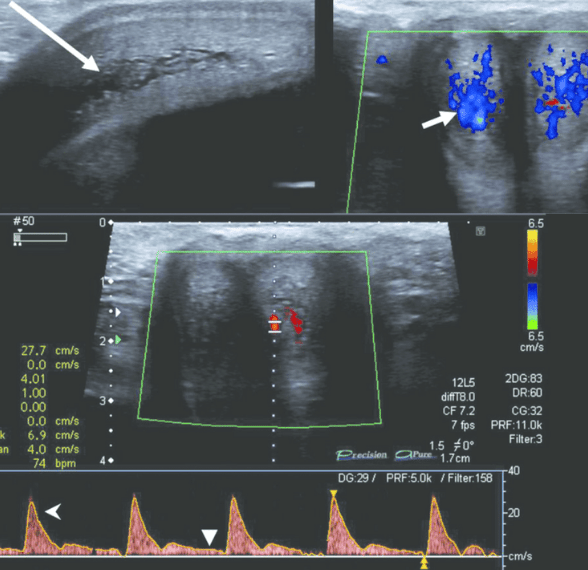

Phương pháp siêu âm Doppler vẫn còn khá mới mẻ với nhiều người. Đây là kỹ thuật dùng hiệu ứng Doppler được sử dụng trực tiếp, có nhiệm vụ chính là kiểm tra, phân tích hình ảnh các bộ phận trên cơ thể. Siêu âm mang đến những hình ảnh sắc nét, giúp bác sĩ chẩn đoán, theo dõi bệnh lý chính xác, nhanh chóng.

Hiện nay, siêu âm Doppler là một trong những kỹ thuật siêu âm hiện đại được áp dụng rộng rãi trong y học do tính hiệu quả cao. Với phương pháp này, bác sĩ có thể phát hiện kịp thời những tổn thương trong cơ thể, có thể kể đến như động mạch thận, động mạch chủ bụng hoặc hệ tĩnh mạch chi dưới. Đặc biệt, nhiều trường hợp nghi ngờ bị tổn thương ở dương vật nên được bác sĩ chỉ định thực hiện siêu âm Doppler dương vật.

Trong các dạng siêu âm Doppler, có hai dạng được áp dụng phổ biến hơn cả đó là siêu âm Doppler xung và siêu âm Doppler màu. Bác sĩ sẽ lựa chọn phương pháp siêu âm dương vật phù hợp, đem lại hiệu quả cao nhất tùy tình trạng sức khỏe của mỗi người.

Siêu âm Doppler dương vật là phương pháp đơn giản, không xâm lấn nhưng giữ vai trò quan trọng trong việc phát hiện và điều trị các bệnh lý liên quan đến bộ phận sinh dục nam. Khi siêu âm dương vật, bác sĩ sẽ siêu âm toàn bộ thân dương vật, bìu,... Siêu âm Doppler dương vật có thể phát hiện một số bệnh lý sau:

Giãn tĩnh mạch thừng tinh: Đây là tình trạng giãn xoắn bất thường ở các tĩnh mạch nằm phía trên tinh hoàn. Do khả năng di chuyển và số lượng tinh trùng giảm đi, giãn tĩnh mạch thừng tinh có thể gây ra vô sinh thứ phát. Khi siêu âm bìu, bác sĩ sẽ quan sát được những đám rối của thừng tinh bị xoắn thành từng búi.

Xoắn tinh hoàn: Đây là một bệnh lý nguy hiểm, dẫn đến biến chứng teo tinh hoàn, hoại tử tinh hoàn nếu không điều trị kịp thời. Thông qua siêu âm bìu, tinh hoàn, các bác sĩ có thể phát hiện mức độ xoắn để có phương án xử lý kịp thời.